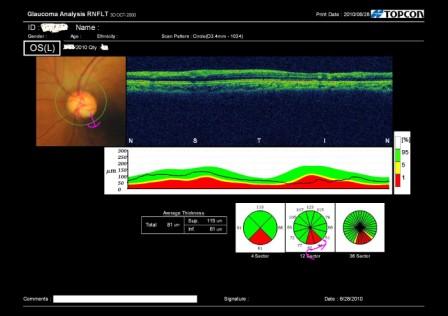

精密検査で視神経の周りの神経繊維層を分析してみると、

やはり両目とも神経の量が減っています。(上記の写真の赤色で示された部分)